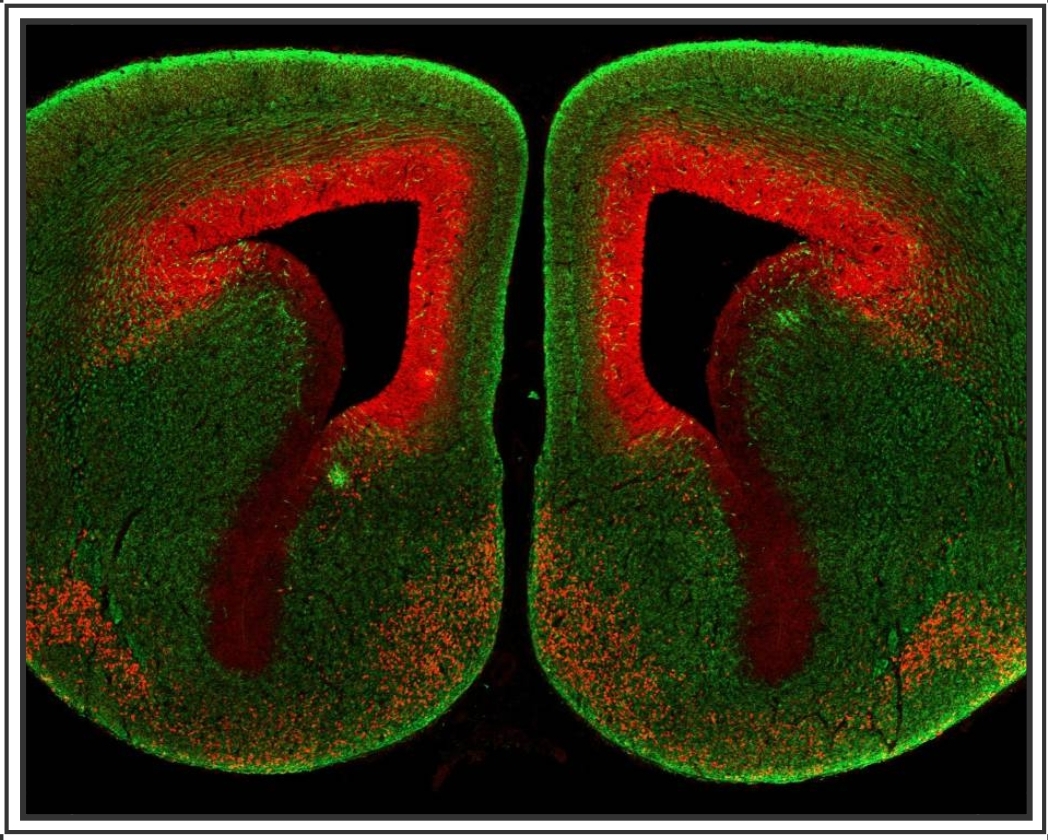

2023级基础学硕王敏:C57BL/6小鼠胚胎大脑切片神经元染色